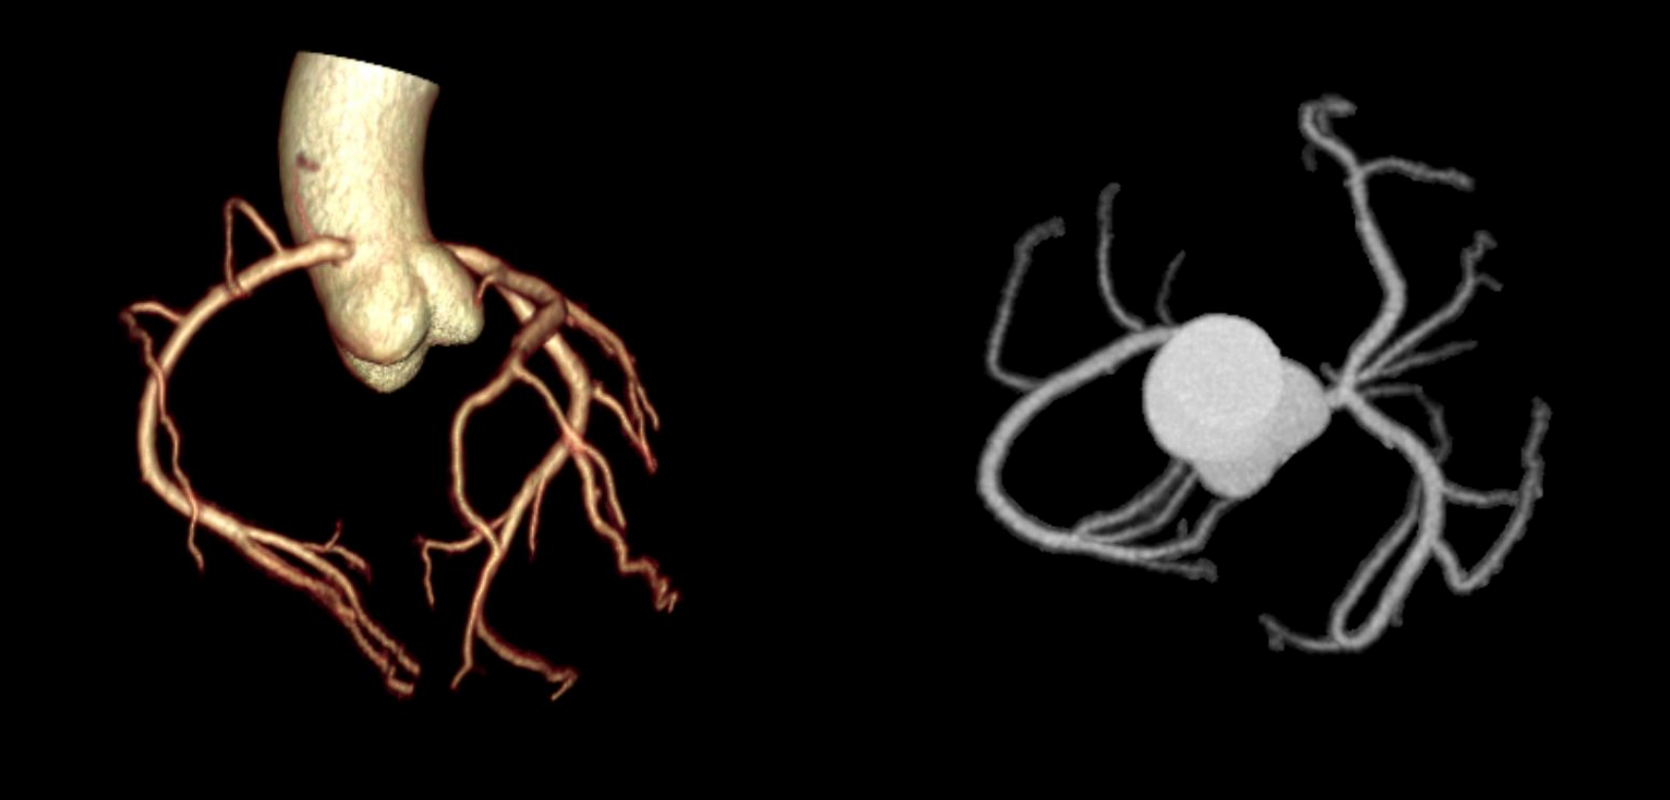

Hệ thống CT tiên tiến này sở hữu tốc độ quay siêu nhanh 0,286 giây, bóng tia X công suất 7,5 MHU (hiệu dụng lên đến 27,1 MHU) cùng detector độ rộng 40 mm. Nhờ các công nghệ hiện đại, hiệu suất chụp tim vượt trội được nâng lên một chuẩn mực mới, mang lại hình ảnh tim mạch chính xác và ổn định. Thiết bị tích hợp nền tảng AI toàn diện, bao phủ toàn bộ quy trình từ định vị bệnh nhân, quét, kiểm soát liều, giảm nhiễu và triệt tiêu artefact đến hậu xử lý hình ảnh và hỗ trợ chẩn đoán, đảm bảo độ chính xác vượt trội ngay cả trong những tình huống lâm sàng phức tạp nhất.